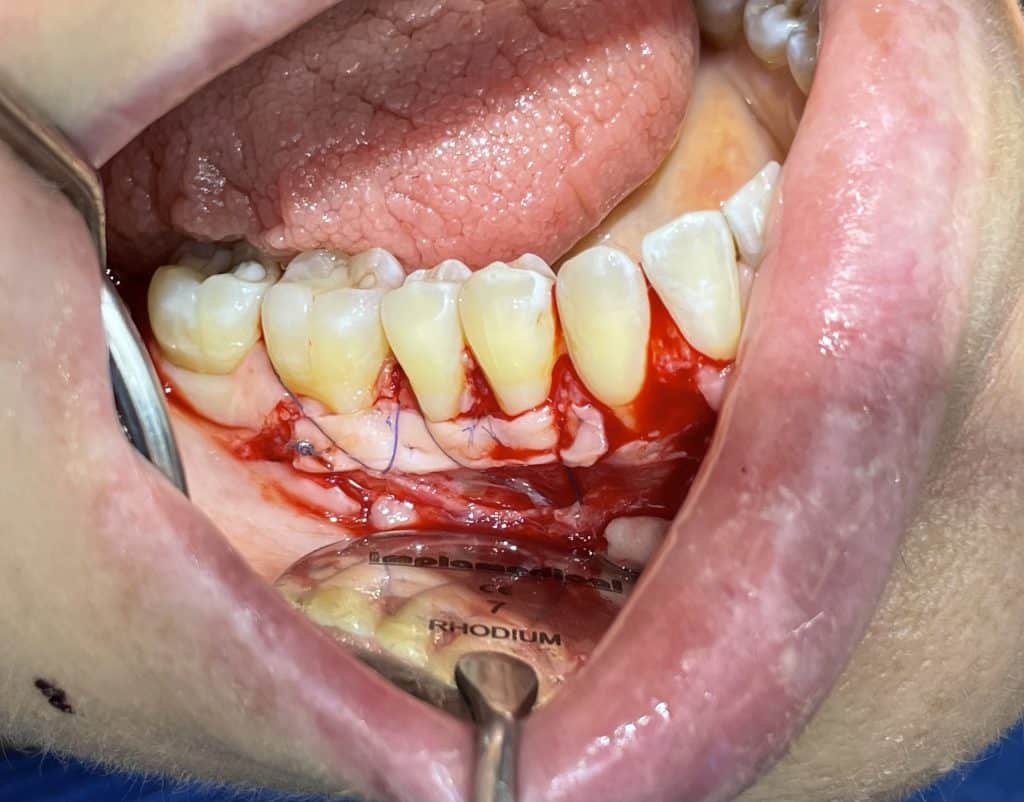

In quadrant 1, we initially removed caries and prepared tooth 14 for subsequent provisional cementation. We then performed a mucogingival surgery procedure, still utilizing the bilaminar technique with an envelope flap. The graft was harvested from the tuberosity area. The connective tissue was sutured to the periosteum, which had been left in place as the recipient bed. The primary flap was advanced coronally, covering the graft, and sutured with sling sutures in the most coronal position. In this case as well, the sutures were removed after 10 days.

the suture of the covering flap in the multiple bilaminar technique